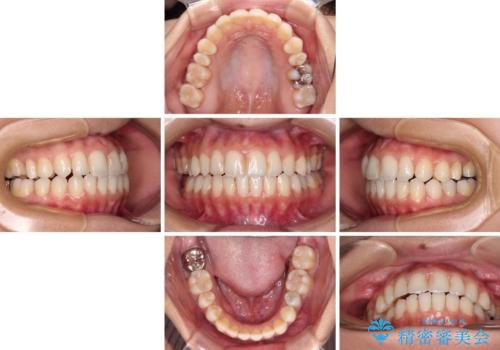

- オープンバイトのため、話しているときの見た目が気になるとのことで来院された患者様です。

下顎骨は左側にシフトしており、咬み合ったときには奥歯と前歯の一部しか接触していない状態でした。

骨格的な左右差は歯列矯正は改善できないため、上下歯列が全体的に接触することをゴールとしてインビザラインにて矯正治療を行うこととしました。

前歯のデコボコの解消と並行して上下の奥歯を圧下させるようにすることで、前歯を接触させるように計画しました。

上下の隙間に舌が入り込むことがオープンバイトの原因であったため、舌の筋肉のトレーニングも並行して行い、後戻りの抑制を図りました。